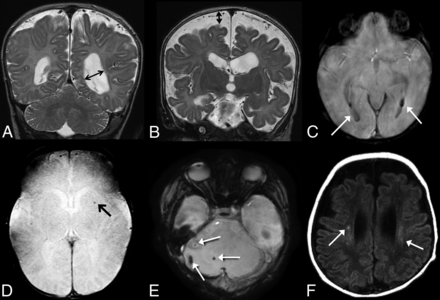

The MR images were independently reviewed by 2 pediatric neuroradiologists who were blinded to the clinical variables except for postmenstrual age at the time of MR imaging. Conflicts were resolved by consensus. The brain was evaluated for evidence of injury and then was scored on the basis of a system modified from previous work by Danzer et al8,10 and Tracy et al.9 Table 1 lists the brain injury scoring guide. The total brain injury score was calculated in each infant. Examples of our scoring system are provided in Fig 2.

A, Coronal T2-weighted image demonstrates ventriculomegaly, scored as grade 2 on our scale; B, Coronal T2-weighted image demonstrates enlarged extra-axial spaces, scored as grade 2 on our scale. C, SWI shows evidence of grade 2 intraventricluar hemorrhage (arrows). D, SWI shows evidence of parenchymal hemorrhage, grade 1 on our scale (arrow). E, SWI shows foci of cerebellar hemorrhage, grade 2 on our scale (arrows). F, Axial T1 weighted images demonstrate foci of bilateral white matter injury, grade 2 on our scale (arrows).